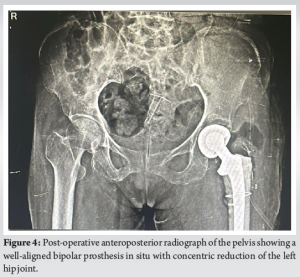

A 76-year-old female patient underwent a left Non-modular unipolar hemiarthroplasty 8 months ago in view of fracture neck of femur, based on the previous scar the procedure was performed through a posterior approach. The patient was able to walk with the help of a walker for 1 month post-surgery after which the patient experienced a sudden shift or slipping sensation in the hip, followed by pain and difficulty moving. At the time of the slippage, the patient did not seek immediate medical attention. Due to limited mobility and lack of access to local orthopedic care, she remained bedridden at home and received only symptomatic treatment in the form of analgesics prescribed by a local physician. No radiographic evaluation or surgical consultation was done until she presented to our outpatient department 8 months post-surgery with chief complaints of persistent left hip pain and restricted mobility and function of the left hip. She was unable to bear weight on her left limb and was bedridden for 7 months. On clinical examination, the left leg was shortened with a limb length discrepancy of 4 cm and was fixed in adduction and internal rotation. The patient was sent for radiographic examination, and a dislocated left hip was confirmed, additionally, they revealed multiple irregular radio-opacities in the acetabular fossa, raising suspicion of cement interposition, retained bony fragments, or intra-articular ossification. The opacities varied in density, with some areas appearing homogeneous and others more fragmented (Fig. 1). A computed tomography scan was considered to better assess cement penetration, retained bone fragments, and acetabular integrity. However, due to financial constraints, further imaging was not pursued. The surgical plan was formulated based on clinical findings and standard radiographs, with intraoperative evaluation guiding implant selection. Pre-operatively, a percutaneous adductor tenotomy was performed to release contractures caused by the chronic dislocation. In addition, skin traction was applied for 2 weeks to help gradually correct limb alignment, reduce muscle stiffness, and facilitate intraoperative reduction. A posterior approach was selected to facilitate access to both the acetabulum and femoral canal while ensuring adequate visualization. Intraoperatively, a well-formed cement mantle was identified conforming to the acetabular shape, confirming cement migration as the underlying pathology. No bony remnants or free-floating osteochondral fragments were observed, effectively ruling out residual femoral head fragments and intra-articular loose bodies. The acetabular walls were intact, and no signs of osteolysis, sequestrum, or infection were observed. The extracted cement was removed en bloc (Fig. 2). A bipolar prosthesis was chosen over total hip replacement (THR) due to the patient’s advanced age, lower functional demands, and intact acetabular wall with no significant erosion or osteolysis. In contrast to the index surgery, meticulous cementing technique was followed. The acetabulum was protected using moist gauze to prevent cement entry, and the cement was introduced only in its doughy phase. The femoral canal was thoroughly prepared, and cement was introduced retrograde with controlled pressurization to achieve a uniform mantle and secure implant fixation. The hip was successfully reduced, ensuring good stability and range of motion (Fig. 3). Given the patient’s advanced age and osteoporotic bone quality, prophylactic cerclage wiring was applied in the subtrochanteric region to reinforce the femur and minimize the risk of intraoperative or post-operative periprosthetic fracture. Thorough irrigation to minimize the risk of infection, careful soft tissue balancing to optimize hip biomechanics, and repair of the posterior capsule to enhance stability were done. Intraoperative assessment confirmed satisfactory positioning of the prosthesis with no undue impingement or instability. Closure was performed in layers, and the patient was stabilized post-operatively. Standard operating procedures were maintained. The immediate post-operative radiograph demonstrated a well-seated bipolar prosthesis with concentric reduction of the hip joint. The acetabular contours appeared intact with no residual cement fragments or signs of joint incongruity. Limb alignment was restored with no limb length discrepancy, and the implant position was stable without evidence of subsidence or malposition (Fig. 4). The patient had a smooth recovery and was discharged 2 weeks after surgery with instructions for partial weight-bearing using bilateral axillary crutches and focusing on restoring hip mobility and muscle strength.